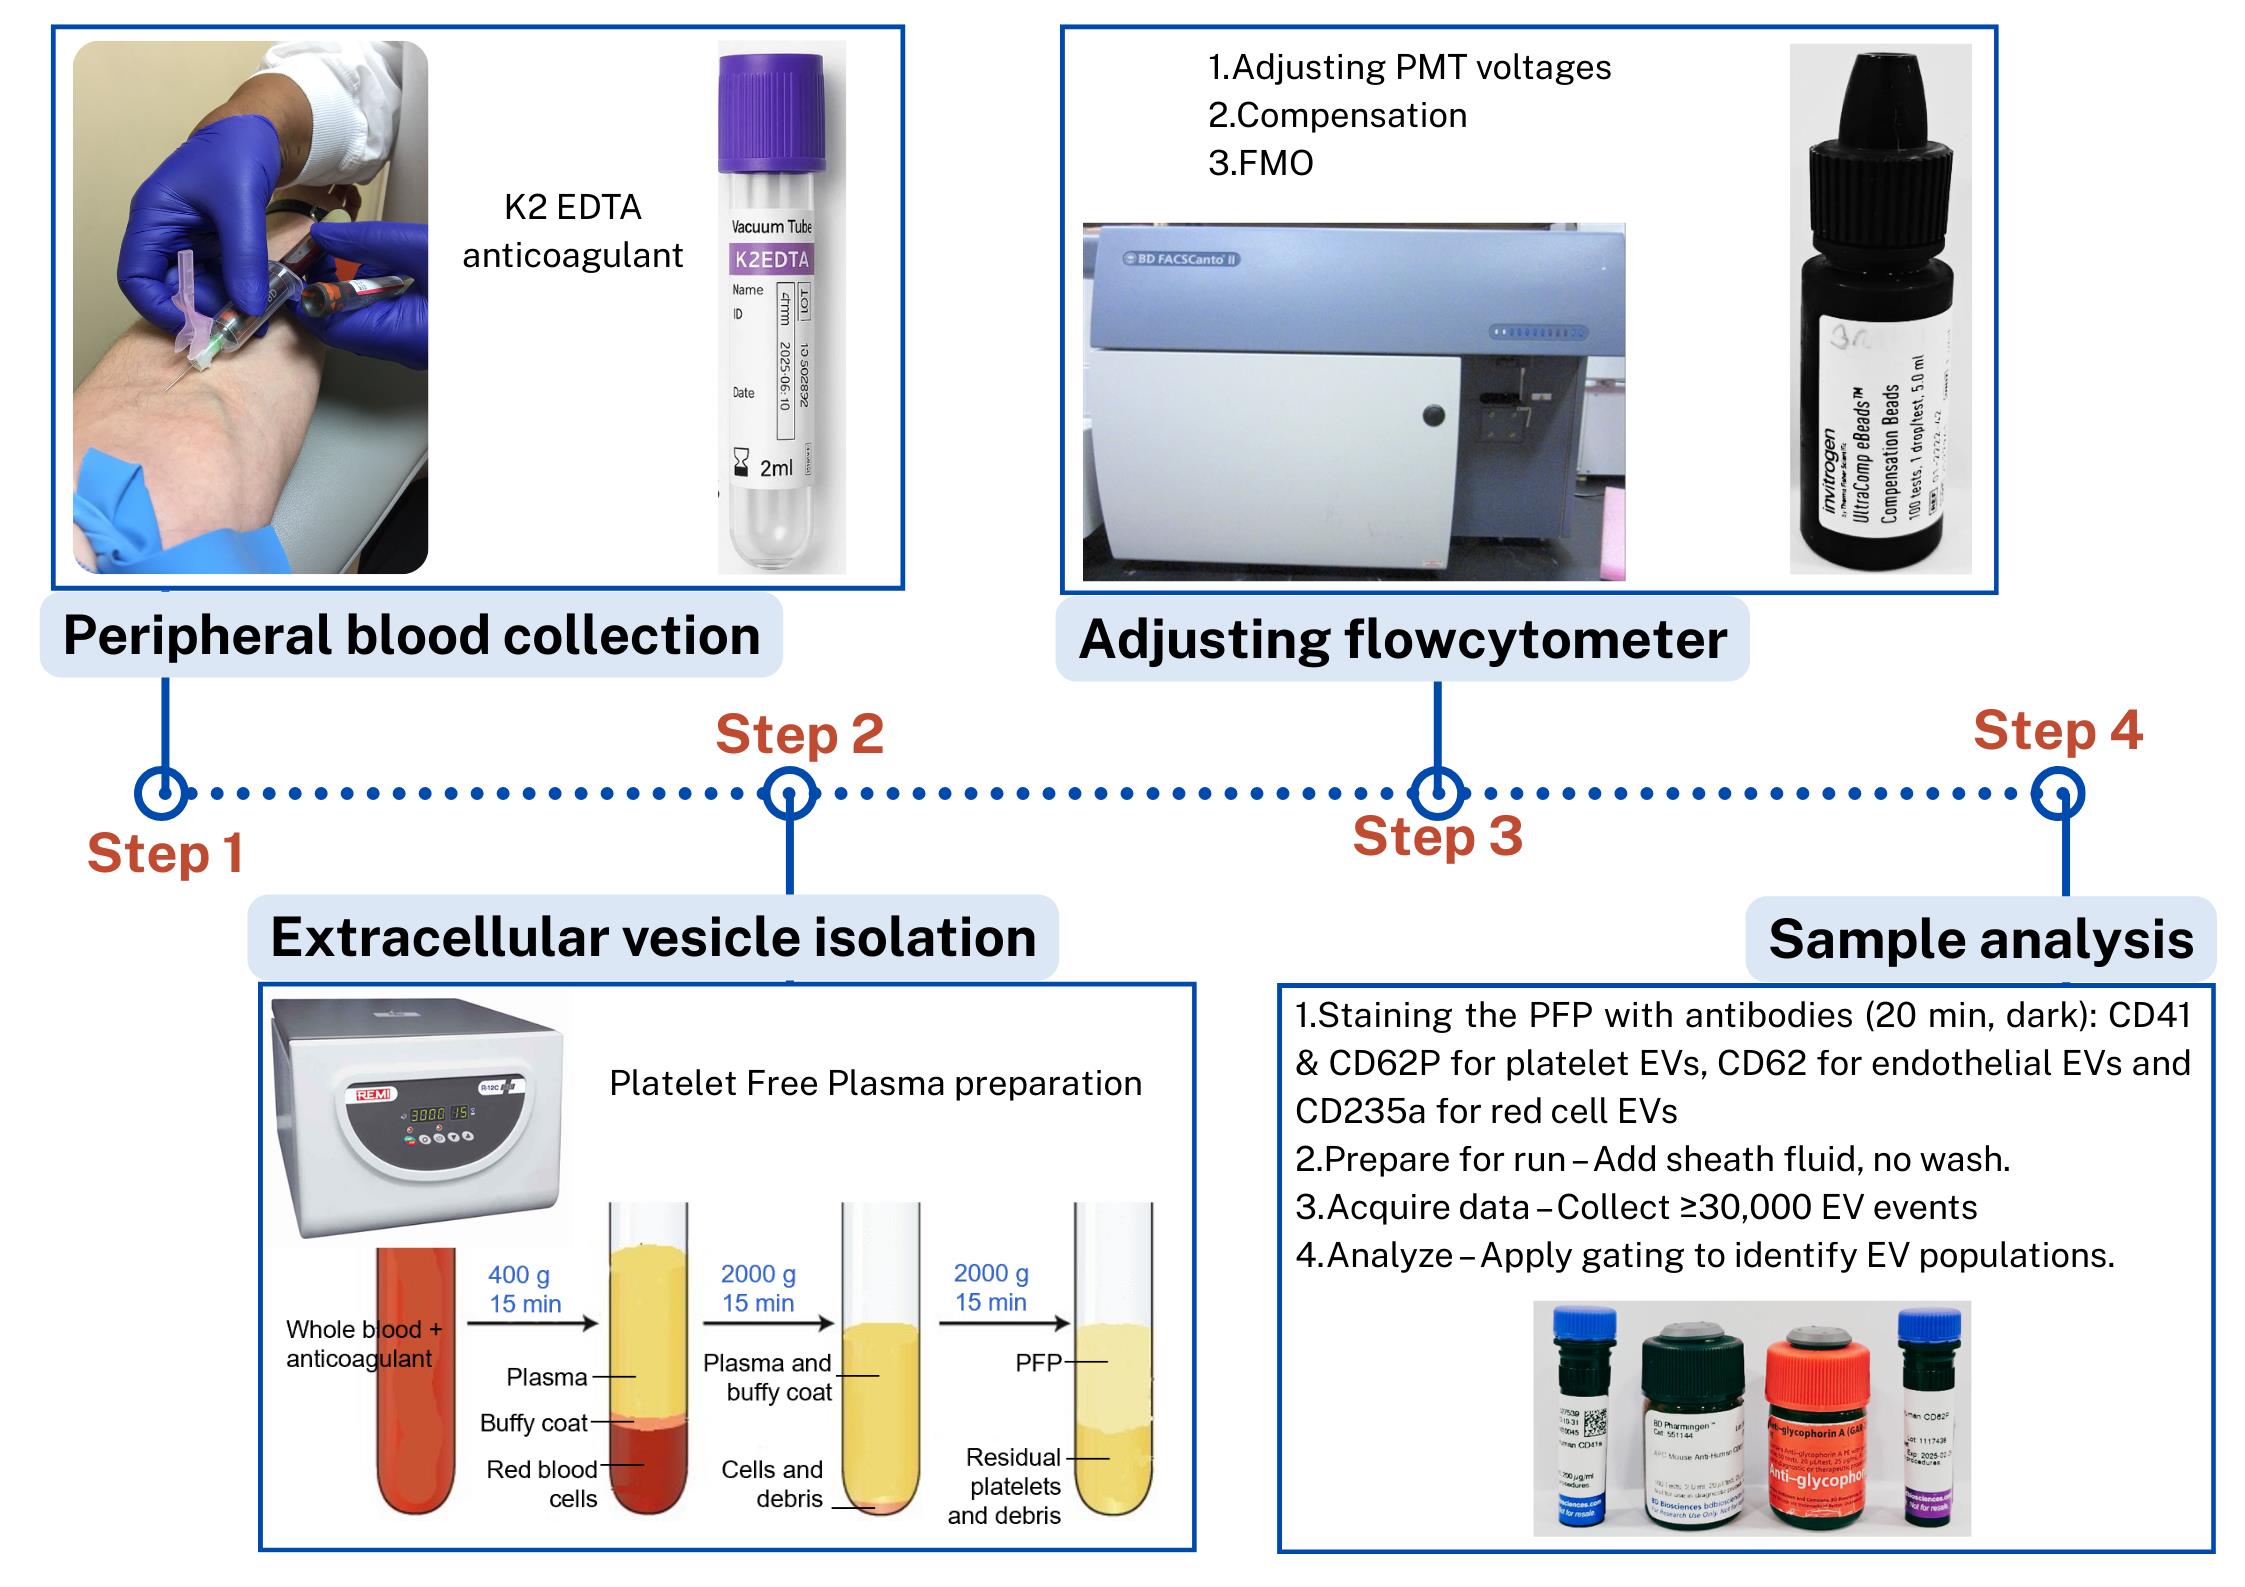

Steps in the isolation and flow cytometric analysis of extracellular vesicles (EVs) derived from red blood cells, endothelial cells, and platelets in human peripheral blood

B. Peripheral blood collection (timing: 10 min)

Note: This step describes the procedure for collecting peripheral whole blood samples from a patient for EV analysis.

1. Collect 3 mL of peripheral blood using a 23-gauge needle and syringe.

2. Transfer blood to a K2-EDTA tube (commercially prepared dipotassium ethylenediaminetetraacetic acid anticoagulant tube) and invert gently 3–4 times until blood and K2-EDTA anticoagulant are well mixed.

3. Perform centrifugation for plasma separation within 4 h of blood collection.

C. Preparation of platelet-free plasma (PFP) (timing: 45 min)

Note: This section describes the procedure for platelet-free plasma (PFP) preparation for isolation of EVs from the whole blood sample.

1. Centrifuge EDTA blood (2 mL) at 400× g for 15 min at room temperature.

2. Transfer supernatant carefully to the plastic round-bottom tube, leaving ~500 μL above the buffy coat so that the red cell pellet and the buffy coat with platelets and white cells are discarded.

3. Centrifuge at 2,000× g for 15 min at room temperature.

4. Transfer supernatant, leaving ~100 μL behind.

5. Perform a final centrifugation at 2,000× g for 15 min.

6. Aliquot the supernatant, leaving ~100 μL behind. EVs are now concentrated in the supernatant, which will be used for analysis. This supernatant is devoid of platelets and hence known as PFP [14].

Critical: The first centrifugation step at a lower speed (typically, 400× g) is performed to remove intact cells and large debris while preventing excessive mechanical stress that could lead to cell lysis and artificial EV release. If a higher speed were used initially, fragile cells, especially platelets, could rupture, artificially increasing EV counts and altering their composition. This low-speed centrifugation effectively separates whole cells from the plasma, ensuring that only naturally circulating EVs remain for subsequent isolation and analysis (Troubleshooting 1).

Note: At each step, new micropipette tips should be used to avoid contamination of cells in the PFP (Figure 1). Care should be taken when removing tubes from the centrifuge, as the layers are easily disturbed; unlike standard cell pellets, EV fractions do not form solid pellets and remain loosely associated with the supernatant (Troubleshooting 2).

Figure 1. Platelet-free plasma (PFP) separation. PFP is the upper 100–200 μL layer, which is devoid of platelets, cell debris, and buffy coat.

D. Adjusting PMT voltages for sample analysis (timing: 1 h)

G. Gating and sample analysis (timing: 25 min)

Note: Gating is crucial for accurately identifying and quantifying specific cell populations within the sample.

1. Transfer 100 μL of PFP into a 5 mL FACS acquisition tube.

2. Add 2 μL of each antibody (CD41A, CD62P, CD62E, CD235a) to the tube. (As EV yield is high in the PFP sample, based on the manufacturer's recommendations, 2 μL of antibody is adequate for optimal staining.)

3. Incubate in the dark for 20 min at room temperature (see Troubleshooting 3).

4. Add 500 μL of sheath fluid and mix gently. (To preserve EV yield, no washing steps are performed. Instead, the sample is diluted in sheath fluid to ensure smooth and consistent aspiration during flow cytometry.)

5. Acquire 30,000 positive events using BD FACSCanto II. Maintain a sample flow rate at a medium setting with a FACS flow pressure of 2.83 × 104 Pa.